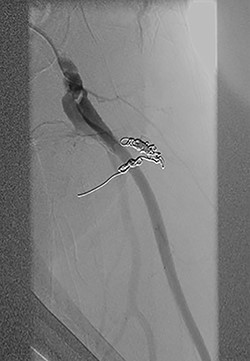

Vascular surgery was consulted and CT angiography demonstrated a large DFA pseudoaneurysm (Fig. 4A and B). Given her advanced years and comorbidities, a minimally invasive approach was recommended. The pseudoaneurysm was successfully embolized using numerous microcoils (Fig. 5). Completion angiography demonstrated complete occlusion of the pseudoaneurysm and patent superficial and DFA (Fig. 5). There were no immediate complications. After discussion with the patient, it was agreed that restarting her apixaban increased risk for her hematoma rebleeding and no anticoagulation was continued for stroke prevention.

Postcoil embolization digitally subtracted angiography via a diagnostic catheter positioned in the left DFA demonstrating adequate embolization of the injured small DFA branch with complete exclusion of the pseudoaneurysm.